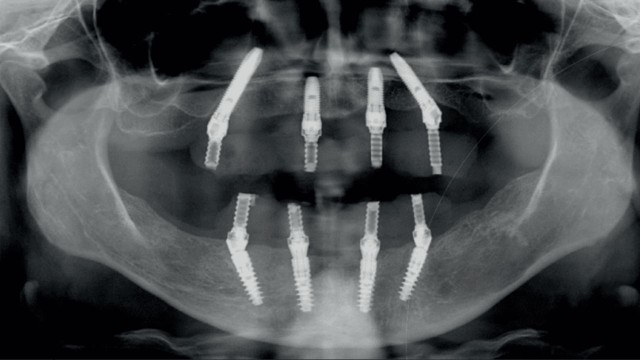

Radiografia post-operatoria, gli impianti distali sono inclinati seguendo il protocollo, i superiori ingaggiano le corticali del seno e gli inferiori emergono in corrispondenza del nervo alveolare, in questo modo è possibile ridurre il cantilever distale della struttura protesica.